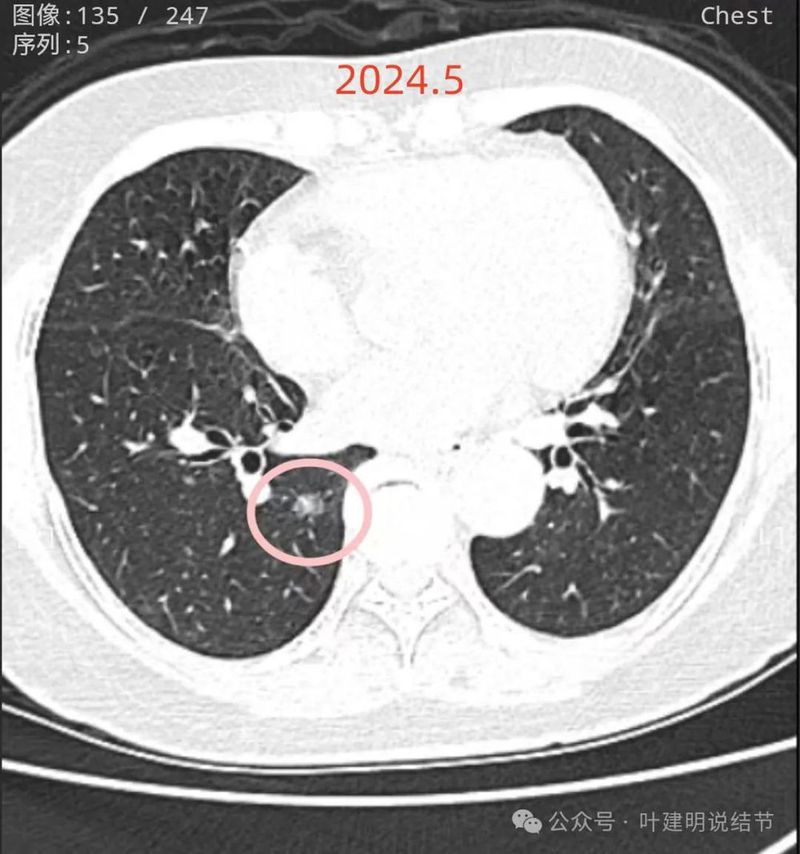

再看2024年5月时的影像:

病灶10:右下叶基底段混合密度结节,有血管穿行,轮廓与边界清,考虑原位癌或微浸润性腺癌可能性大。

两肺多发磨玻璃结节,部分是混合密度。主病灶是红色这处在左上叶的,对比2021年有明显增大进展,考虑是浸润性腺癌可能性大,或者微浸润性腺癌;粉色的考虑原位癌可能性大;橘色的考虑不典型增生可能性大;黄色的考虑肺泡上皮增生可能性大;紫色的考虑微浸润性腺癌可能性大;绿色的考虑良性的可能性大;蓝色的考虑浸润性腺癌或者微浸润性腺癌;黑色的是2021年的时候比较明显的几处病灶。总体对比来看红色的范围增大比较明显,实性成分也有增加;蓝色的密度增加比较明显。首先考虑是多原发早期肺癌。个人觉得继续随访存在一定风险,当然由于病灶太多,也不是说都靠外科手术能够解决问题的,但是主要的有风险的病灶如果能够手术还是需要手术先解决,其他次要的病灶后续再考虑消融或者其他治疗。我的想法是先做右肺下叶背段切除(紫色,考虑微浸润或浸润)加上叶楔形切除(蓝色),下叶粉色的也可楔切或不切;之后看恢复情况过三个月左右再做左肺上叶切除。其余病灶后续如果随访进展考虑消融控制。意见供参考!为何先建议做右侧:先做右侧是因为右侧切得少,到时候再切左侧的时候,单肺通气更能耐受。如果先做左侧,下次做右侧时,左下叶单肺通气不太能耐受些。而且蓝色这处密度增加明显,又贴着胸膜,它的风险相对来说也较高,或许比左上红色的还高点。所以先做右侧。若非转移,靶向药个人不太建议吃,又不是晚期,是多原发早期肺癌可能性大呀。